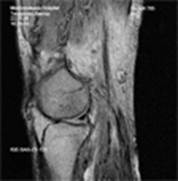

Сравнение рентгеновского снимка и МР томограммы коленного сустава.

Примеры томограмм

| Аксиальные проекции | Сагиттальные проекции | Коронарные проекции |